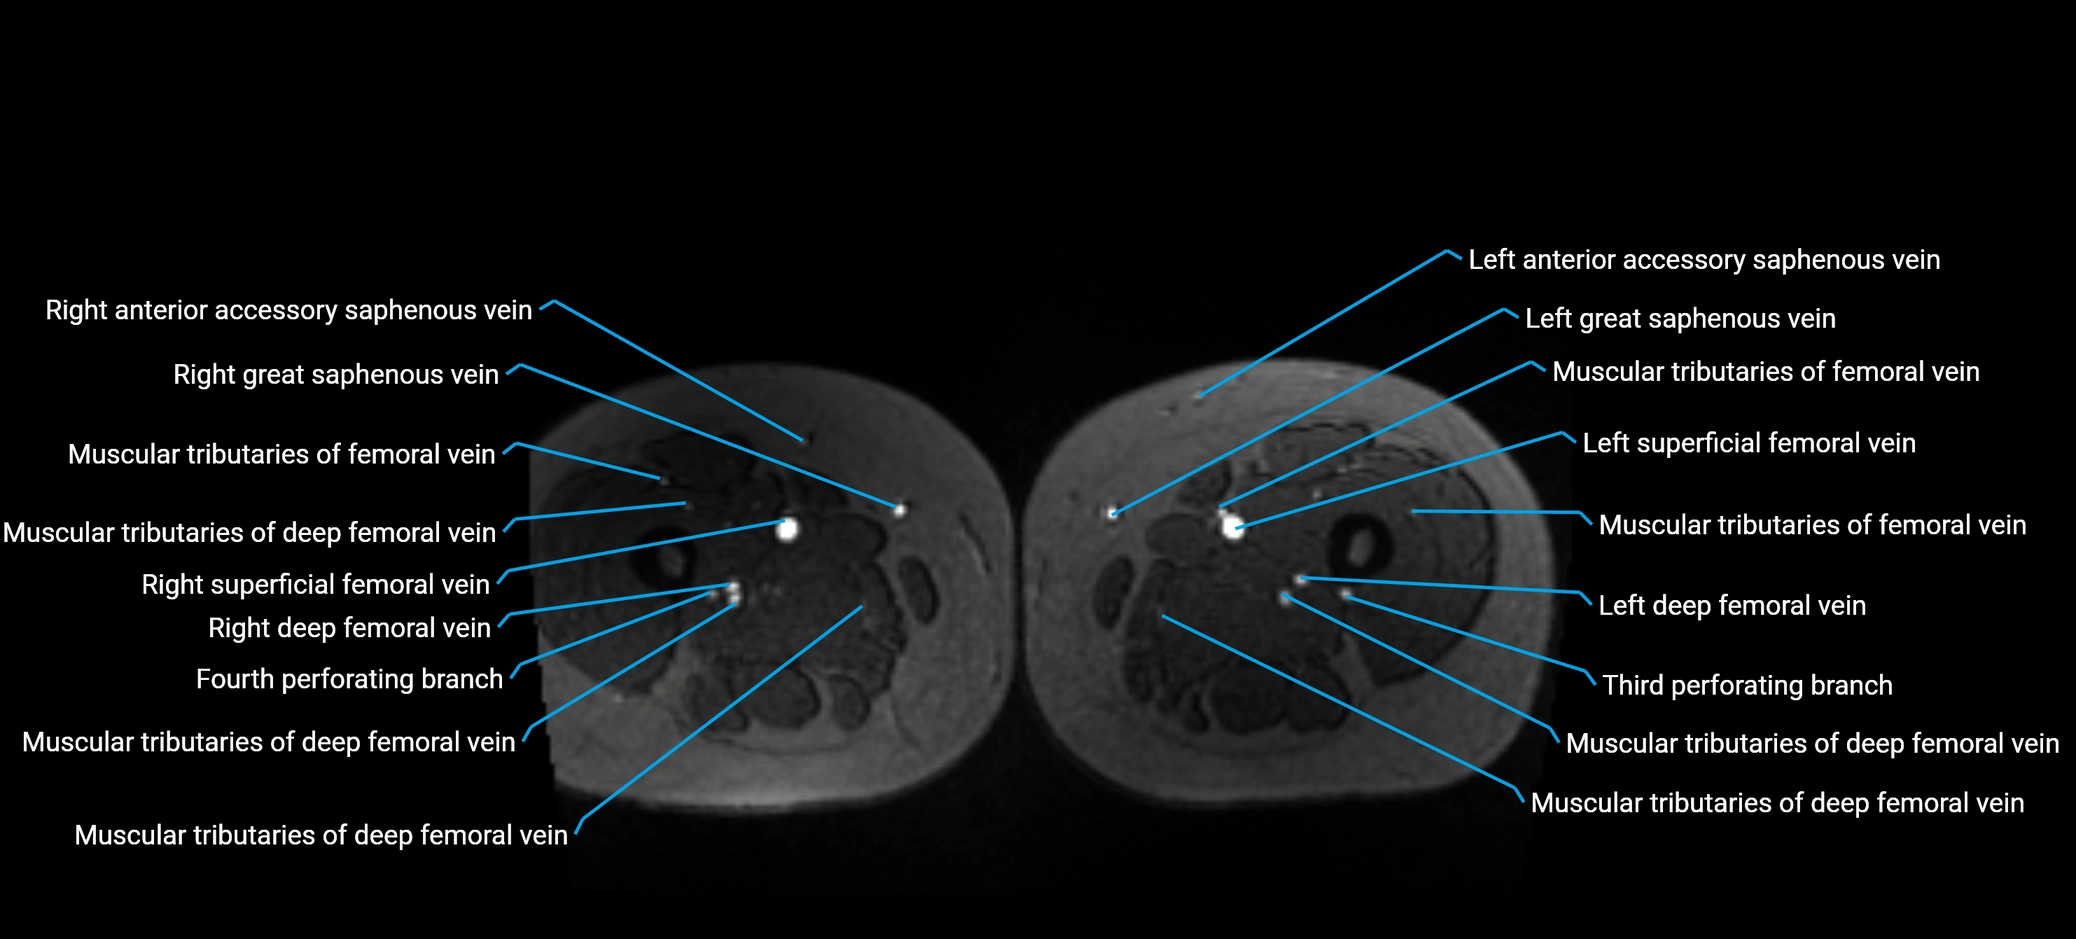

MRI image

image